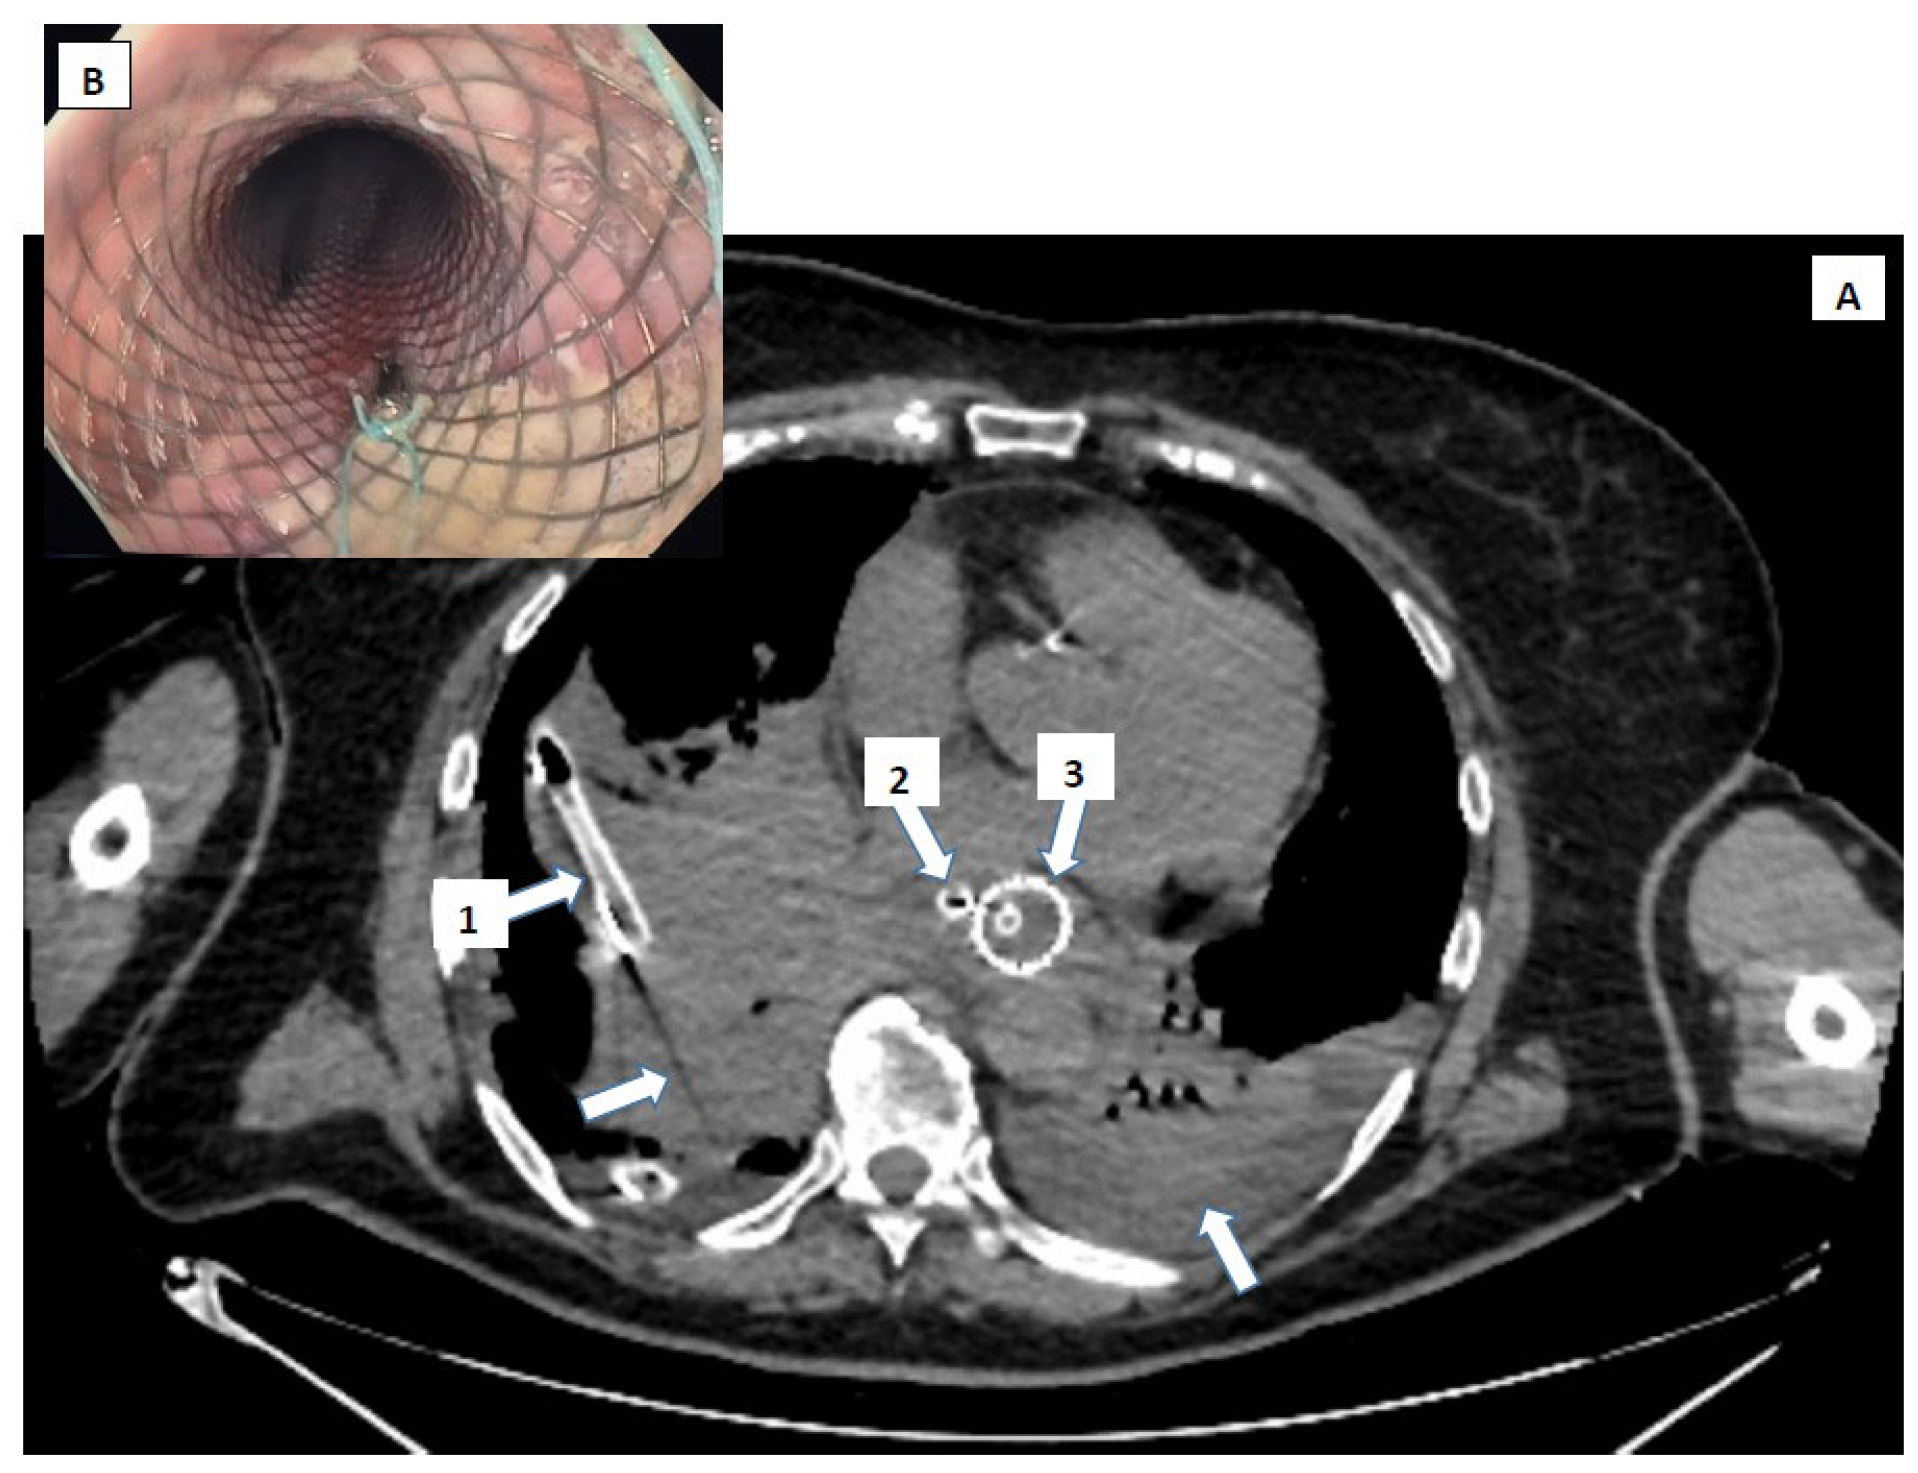

- In two cases, the resolution was strictly gastroenterological (stenting) combined with sustained intensive care support.

- In the fifth case, a combined approach was used—endoscopical (stenting) and surgical (thoraco-laparoscopic) interventions performed in the same therapeutic session, a so-called “rendez-vous” procedure.

9.4. Stent Placement

9.5. Combined Vacuum-Stent Therapy

- Nasa, M.; Sharma, Z.D.; Choudhary, N.S.; Puri, R.; Sud, R. Removable self-expanding metal stents insertion for the treatment of perforations and postoperative leaks of the esophagus. Indian J. Gastroenterol. 2016, 35, 101–105. [Google Scholar] [CrossRef] [PubMed]

- Kopelman, Y.; Abu Baker, F.; Troiza, A.; Hebron, D. Boerhaave syndrome in an elderly man successfully treated with 3-month indwelling esophageal stent. Radiol. Case Rep. 2018, 13, 1084–1086. [Google Scholar] [CrossRef]

- Margaris, I.; Triantafyllou, T.; Sidiropoulos, T.A.; Sideris, G.; Theodorou, D.; Arkadopoulos, N.; Michalopoulos, N.V. Efficacy of esophageal stents as a primary therapeutic option in spontaneous esophageal perforations: A systematic review and meta-analysis of observational studies. Ann. Gastroenterol. 2024, 37, 156–171. [Google Scholar] [CrossRef]

- Fawwaz, B.A.B.; Gerges, P.; Singh, G.; Rahman, S.H.; Al-Dwairy, A.; Mian, A.; Khan, N.; Syndrome, A.F.B. A Report of Two Cases and Literature Review. Cureus 2022, 14, e25241. [Google Scholar] [CrossRef] [PubMed]

- Dasari, B.V.; Neely, D.; Kennedy, A.; Spence, G.; Rice, P.; Mackle, E.; Epanomeritakis, E. The role of esophageal stents in the management of esophageal anastomotic leaks and benign esophageal perforations. Ann. Surg. 2014, 259, 852–860. [Google Scholar] [CrossRef]

- Talbot, M.; Yee, G.; Saxena, P. Endoscopic modalities for upper gastrointestinal leaks, fistulae and perforations. ANZ J. Surg. 2017, 87, 171–176. [Google Scholar] [CrossRef]

- Hauge, T.; Kleven, O.C.; Johnson, E.; Hofstad, B.; Johannessen, H.-O. Outcome after stenting and débridement for spontaneous esophageal rupture. Scand. J. Gastroenterol. 2018, 53, 398–402. [Google Scholar] [CrossRef]

- Chirica, M.; Kelly, M.D.; Siboni, S.; Aiolfi, A.; Riva, C.G.; Asti, E.; Ferrari, D.; Leppäniemi, A.; Broek, R.P.G.T.; Brichon, P.Y.; et al. Esophageal emergencies: WSES guidelines. World J. Emerg. Surg. 2019, 14, 1–15. [Google Scholar] [CrossRef]

- Ong, G.K.; Freeman, R.K. Endoscopic management of esophageal leaks. J. Thorac. Dis. 2017, 9, S135–S145. [Google Scholar] [CrossRef]

- Bludevich, B.M.; Palleiko, B.A.; Reddington, H.; Navarro, M.; Uy, S.A.Q.; Maxfield, M.W.; Emmerick, I.; Lou, F.; Uy, K.F.L. Safety of long-term esophageal stent use for multiple indications. J. Thorac. Dis. 2024, 16, 4208–4216. [Google Scholar] [CrossRef]